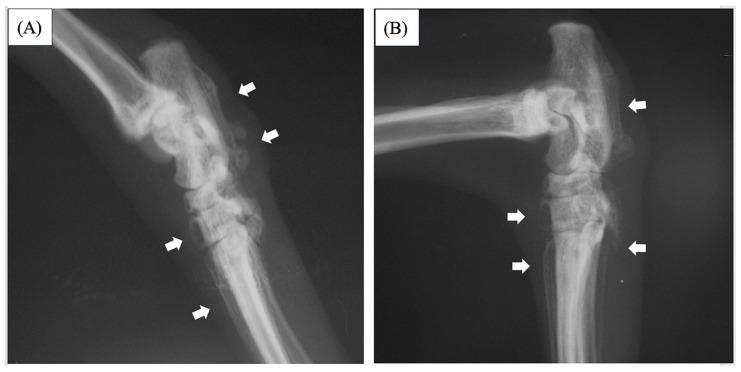

An eight-year-old spayed female Abyssinian cat presented with lameness. Palpation revealed swelling, heat, and a reduced range of motion in the stifle and tarsal joints in both hind limbs. A radiographic examination of both hind limbs revealed periosteal proliferation from the distal tibia to the tarsal and metatarsal bones, which suggested hypertrophic osteopathy. Thorax and abdominal radiographic examinations were performed to identify the primary disease. Complete blood count and routine serum biochemistry tests revealed no abnormalities. No obvious anomalies were evident in the thoracic radiograph; however, a mass was observed near the left kidney on an abdominal radiograph. An abdominal ultrasound was performed, which revealed a hypoechoic renal mass located in the caudal pole of the left kidney. The left nephrectomy was performed after exploration of the abdominal cavity confirmed an abnormality in the left kidney. A histopathological examination revealed renal cell carcinoma. The cat was subsequently fed on a renal prescription diet but received no additional treatment. The periosteal lesion in the distal tibia regressed over time, but the lesions remained in the talus and metatarsal bones. At 1670 days following surgery, blood tests indicated that urea nitrogen and creatinine were above the normal range. In addition, urinalysis revealed an isosthenuria. However, the cat survived over 4500 days following surgery.

一只八岁已绝育的雌性阿比西尼亚猫出现跛行症状。触诊发现双后肢的膝关节和跗关节肿胀、发热且活动范围减小。对双后肢进行的X线检查显示,从胫骨远端到跗骨和跖骨有骨膜增生,提示肥大性骨关节病。进行胸部和腹部X线检查以确定原发性疾病。全血细胞计数和常规血清生化检查未发现异常。胸部X线片未见明显异常;然而,腹部X线片上在左肾附近观察到一个肿块。进行了腹部超声检查,发现左肾尾极有一个低回声肾肿块。在探查腹腔证实左肾有异常后,进行了左肾切除术。组织病理学检查显示为肾细胞癌。这只猫随后食用肾脏处方饮食,但未接受其他治疗。胫骨远端的骨膜病变随时间消退,但距骨和跖骨的病变仍然存在。术后1670天时,血液检查表明尿素氮和肌酐高于正常范围。此外,尿液分析显示等渗尿。然而,这只猫术后存活了超过4500天。